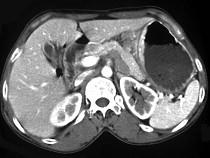

问题 女,56岁,上腹部钝痛、腹胀不适1月余,纳差、消瘦,影像检查如图,最可能的诊断是()

选项 A.胃幽门管溃疡 B.胃腺癌并幽门狭窄 C.胃淋巴瘤 D.胃间质瘤 E.胃恶性间质瘤

答案 B